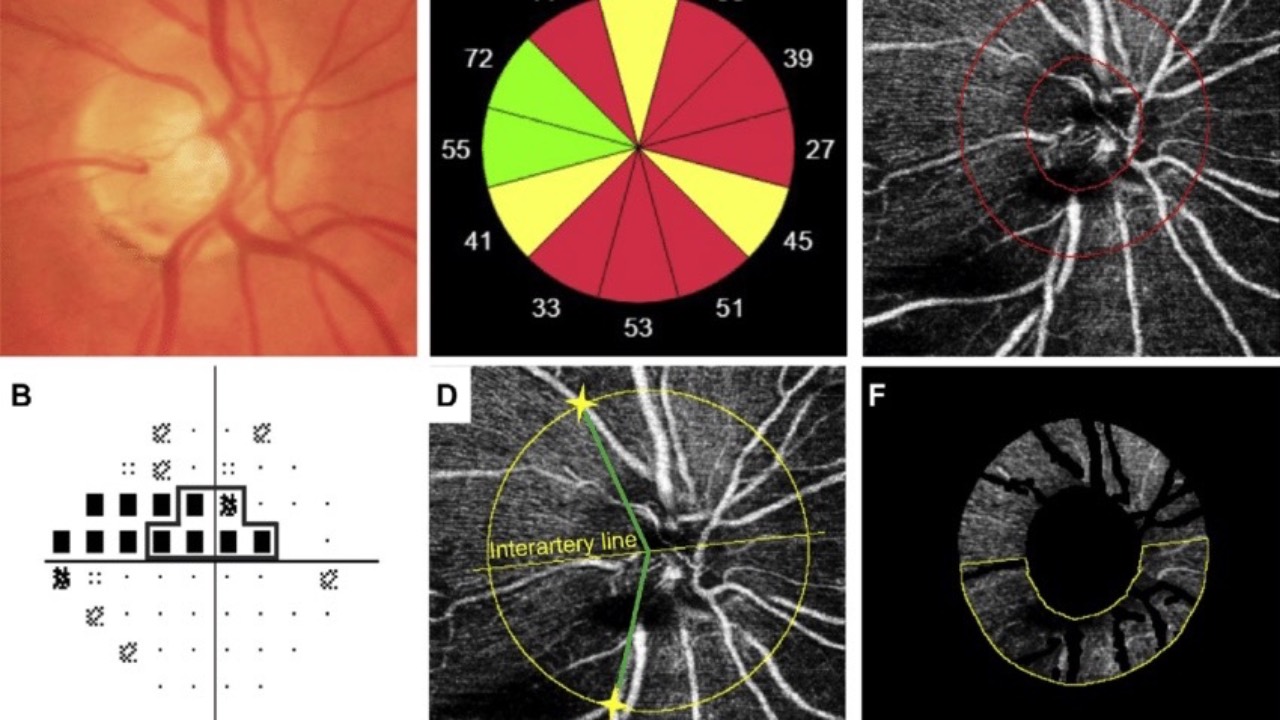

Retinal O2 Saturation & Glaucomatous VF Defects

The Journal of Glaucoma recently published findings which found a counterintuitive relationship but significant correlation between retinal oxygen saturation (StO2) and the severity of visual field loss in glaucoma patients.

A study utilizing novel diffuse reflectance spectroscopy found higher...